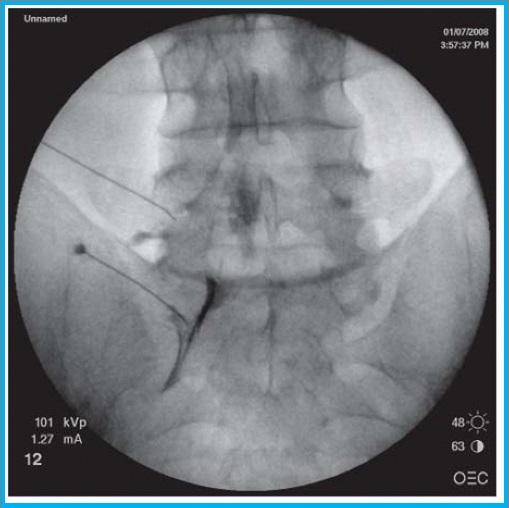

Στην ουραία επισκληρίδιο έγχυση υπό ακτινοσκοπική καθοδήγηση, εισάγεται ένας καθετήρας μέσω του ιερού τρήματος και προωθείται έως το επίπεδο στης κατώτερης οσφυϊκής μοίρας, όπου γίνεται η έγχυση διαλύματος τοπικού αναισθητικού και στεροειδούς.

Στην διατρηματική έγχυση, υπό ακτινοσκοπική καθοδήγηση, το φαρμακευτικό διάλυμα χορηγείται απευθείας στο σημείο εξόδου της νευρικής ρίζας, για την αντιμετώπιση του ριζιτικού άλγους.

Πρόκειται για μια ελάχιστα επεμβατική πράξη, όπου μια ειδική βελόνα με ενσωματωμένο ηλεκτρόδιο εισάγεται στο σπονδυλικό τρήμα στο επίπεδο του ραχιαίου γαγγλίου της οπίσθιας ρίζας. με χρήση παλμικής ραδιοσυχνότητας γίνεται η διέγερση του γαγγλίου, με στόχο την τροποποίηση της μεταφοράς και αντίληψης των επώδυνων μηνυμάτων.